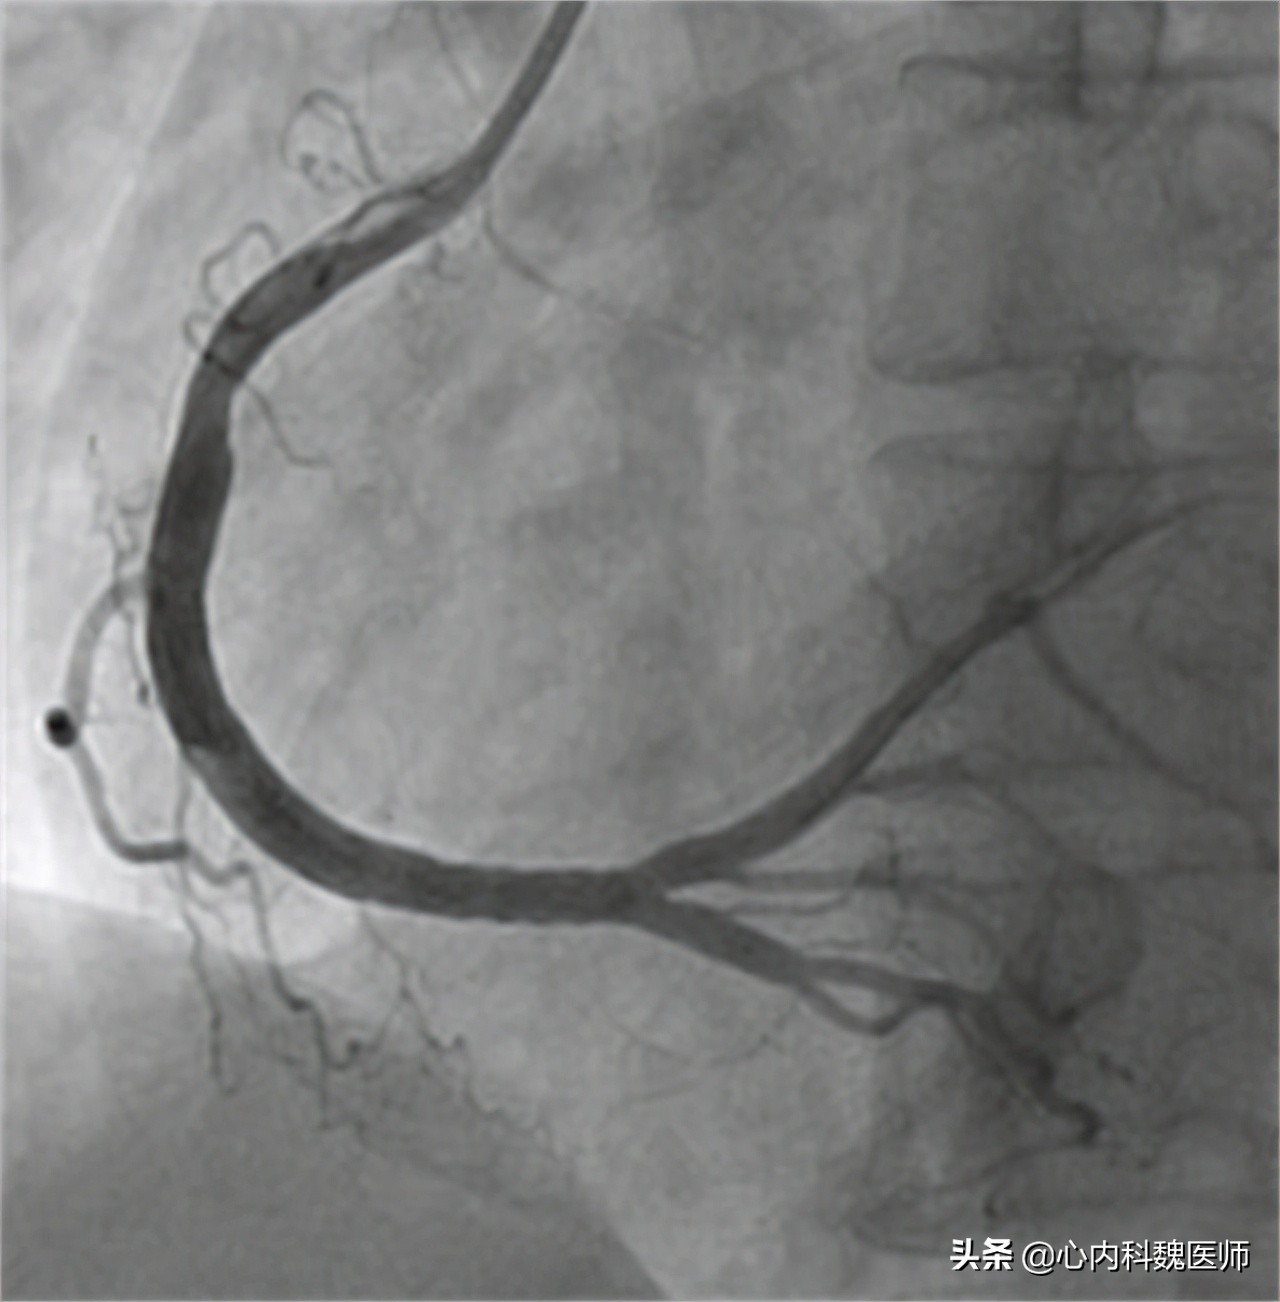

高大爷向医生说明了自己8年的冠心病史和一直没有服用药物的状态,医生害怕高大爷的病情进一步加重,于是做了简单的查体后就安排了高大爷住院进行心脏冠脉造影的检查。检查结果出来后,医生十分奇怪高大爷的情况。

医生:“大爷,根据您造影的情况,冠状动脉堵塞还不到 百分之二十五 ,远够不上冠心病的标准啊,到底是谁告诉您有冠心病的?”

患者体温36.5℃、血压130/90、身高168cm、体重68kg。心电图提示心脏存在明显早搏现象。心脏造影显示主动脉堵塞百分之二十三,排除冠心病。

医生:“冠心病的最佳诊断方法就是做 冠状动脉造影 ,因为这是最直观观察冠状动脉情况的检查。但是鉴于这种检查对患者会导致一定的创伤,所以我们只有在高度怀疑患者有冠心病的时候才会考虑。”

医生:“还有一种检查被叫做 冠脉CT ,这种检查虽然没有造影那么直观,但是可以作为辅助诊断冠心病的检查,当检查结果提示患者的冠状动脉重度狭窄时,大概率就是冠心病的症状,如果需要进一步确诊可以再考虑冠状动脉造影,检查具体堵塞的位置。”